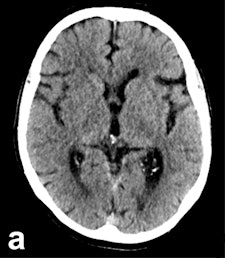

In large clinical studies, thrombectomy has been used mainly in patients whose CTs show a lower degree of severity, normally assessed using the Alberta Stroke Program Early CT Score (ASPECTS). In most of the successful studies, including ESCAPE, SWIFT PRIME, and REVASCAT, the ASPECTS must be no worse than six or seven points out of 10.

ASPECTS scoring is standard in patients who undergo CT for a recent stroke. "Doing the scores manually requires a high degree of experience, and is prone to error," Herweh said, adding that this problem can be solved by using software to calculate the scores. "It's more objective, and may be better than radiologists at evaluating patients' prognoses."

The Brainomix eASPECTS software, which has been around for some time now, is increasingly proving its value in clinical studies.

An initial validation study of 34 patients by the Heidelberg group showed that software evaluation of CT images was better than assessments by radiologists with limited training, and performed to the same level as experts. Furthermore, a U.K. study of 132 patients showed the software was at least equal to neuroradiologists, he explained.

It works from a technical viewpoint, but the key clinical question is whether this method is better than, or as good as, experts at predicting which patients have a poor prognosis. Therefore, Herweh and his colleagues carried out a third study of 212 recent stroke patients, using three experts and the software to calculate the ASPECTS retrospectively. The result was then correlated with the patients' actual clinical progress.

"What we've shown is that the software reliably predicts a poor prognosis following thrombectomy," he stated.

A low eASPECTS has a statistically significant correlation to such a prognosis. Among experts, however, this correlation was statistically significant in only one out of three cases. In other words, software-based scoring could be more objective and clinically conclusive than manual scoring by experts.